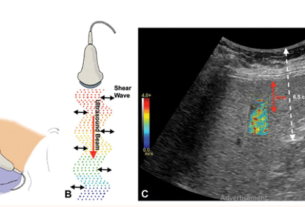

- Doppler Ultrasound Scanner

- Measures blood flow in abdominal vessels.

- Helps detect blockages, reduced blood flow, or aneurysms in major vessels like the aorta.